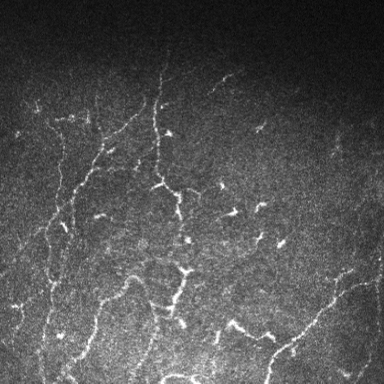

Chronic diseases are notoriously age related, recalcitrant, and incurable, but they benefit from long-term therapy, Dr. Sheppard said. The classic examples are glaucoma and dry eye, and many in this cohort also have cataracts. These patients require intervention for long periods of time, and continuous use of preserved glaucoma medications are known to create changes in the ocular surface.

glaucoma medication use

Source: Anat Galor, MD, MSPH

He added that infiltration of inflammatory cells into the conjunctiva can cause a hypersensitivity reaction that can be exacerbated by the preservative themselves. Patients who have sensitivities to the active ingredient may become even more sensitive because the preservative is a well-known way to enhance permeability, so medications with continuous insult to the ocular surface are more efficacious because they enter the corneal or conjunctival tissues more readily. On the other hand, you have to be very cautious in this population because they tend to be older, and therefore more likely at risk for dry eye disease and trabecular meshwork outflow damage.